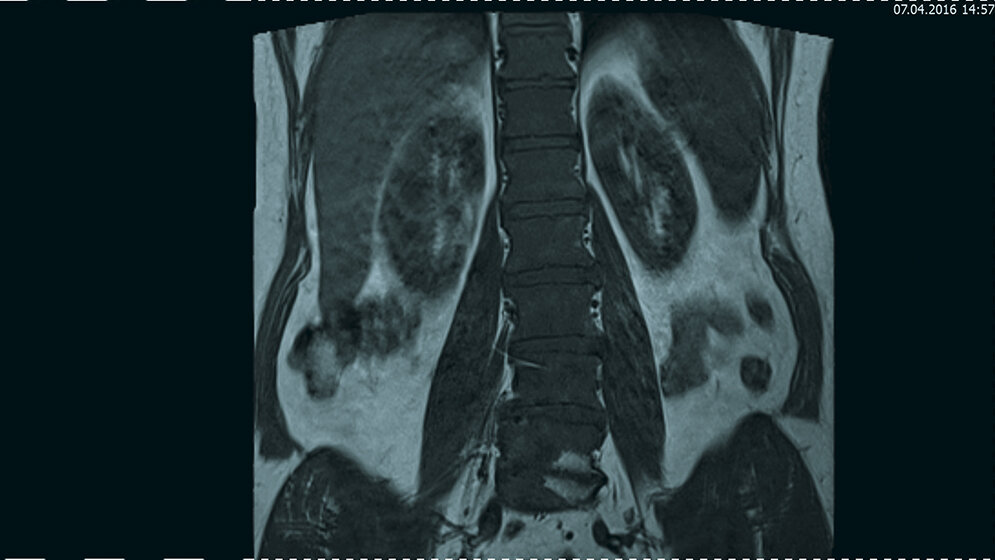

Tumoröse Veränderungen: Polyzythämia vera

Extramedulläres hämatopoetisches Gewebe mit Ausdehnung im Spinalkanal und Kompression des Myelon ist selten. Im Fall der extramedullären Hämatopoese bei Patienten mit Polyzythämia vera kann eine frühe Diagnosestellung eine sehr gute Prognose geben. Die klinische Symptomatik, Kenntnis der Erkrankung und der bildgebenden Aspekte sind wichtig für die Diagnose. Die MRT ist die bildgebende Methode für die Primärdiagnostik der extra-medullären Hämatopoese.